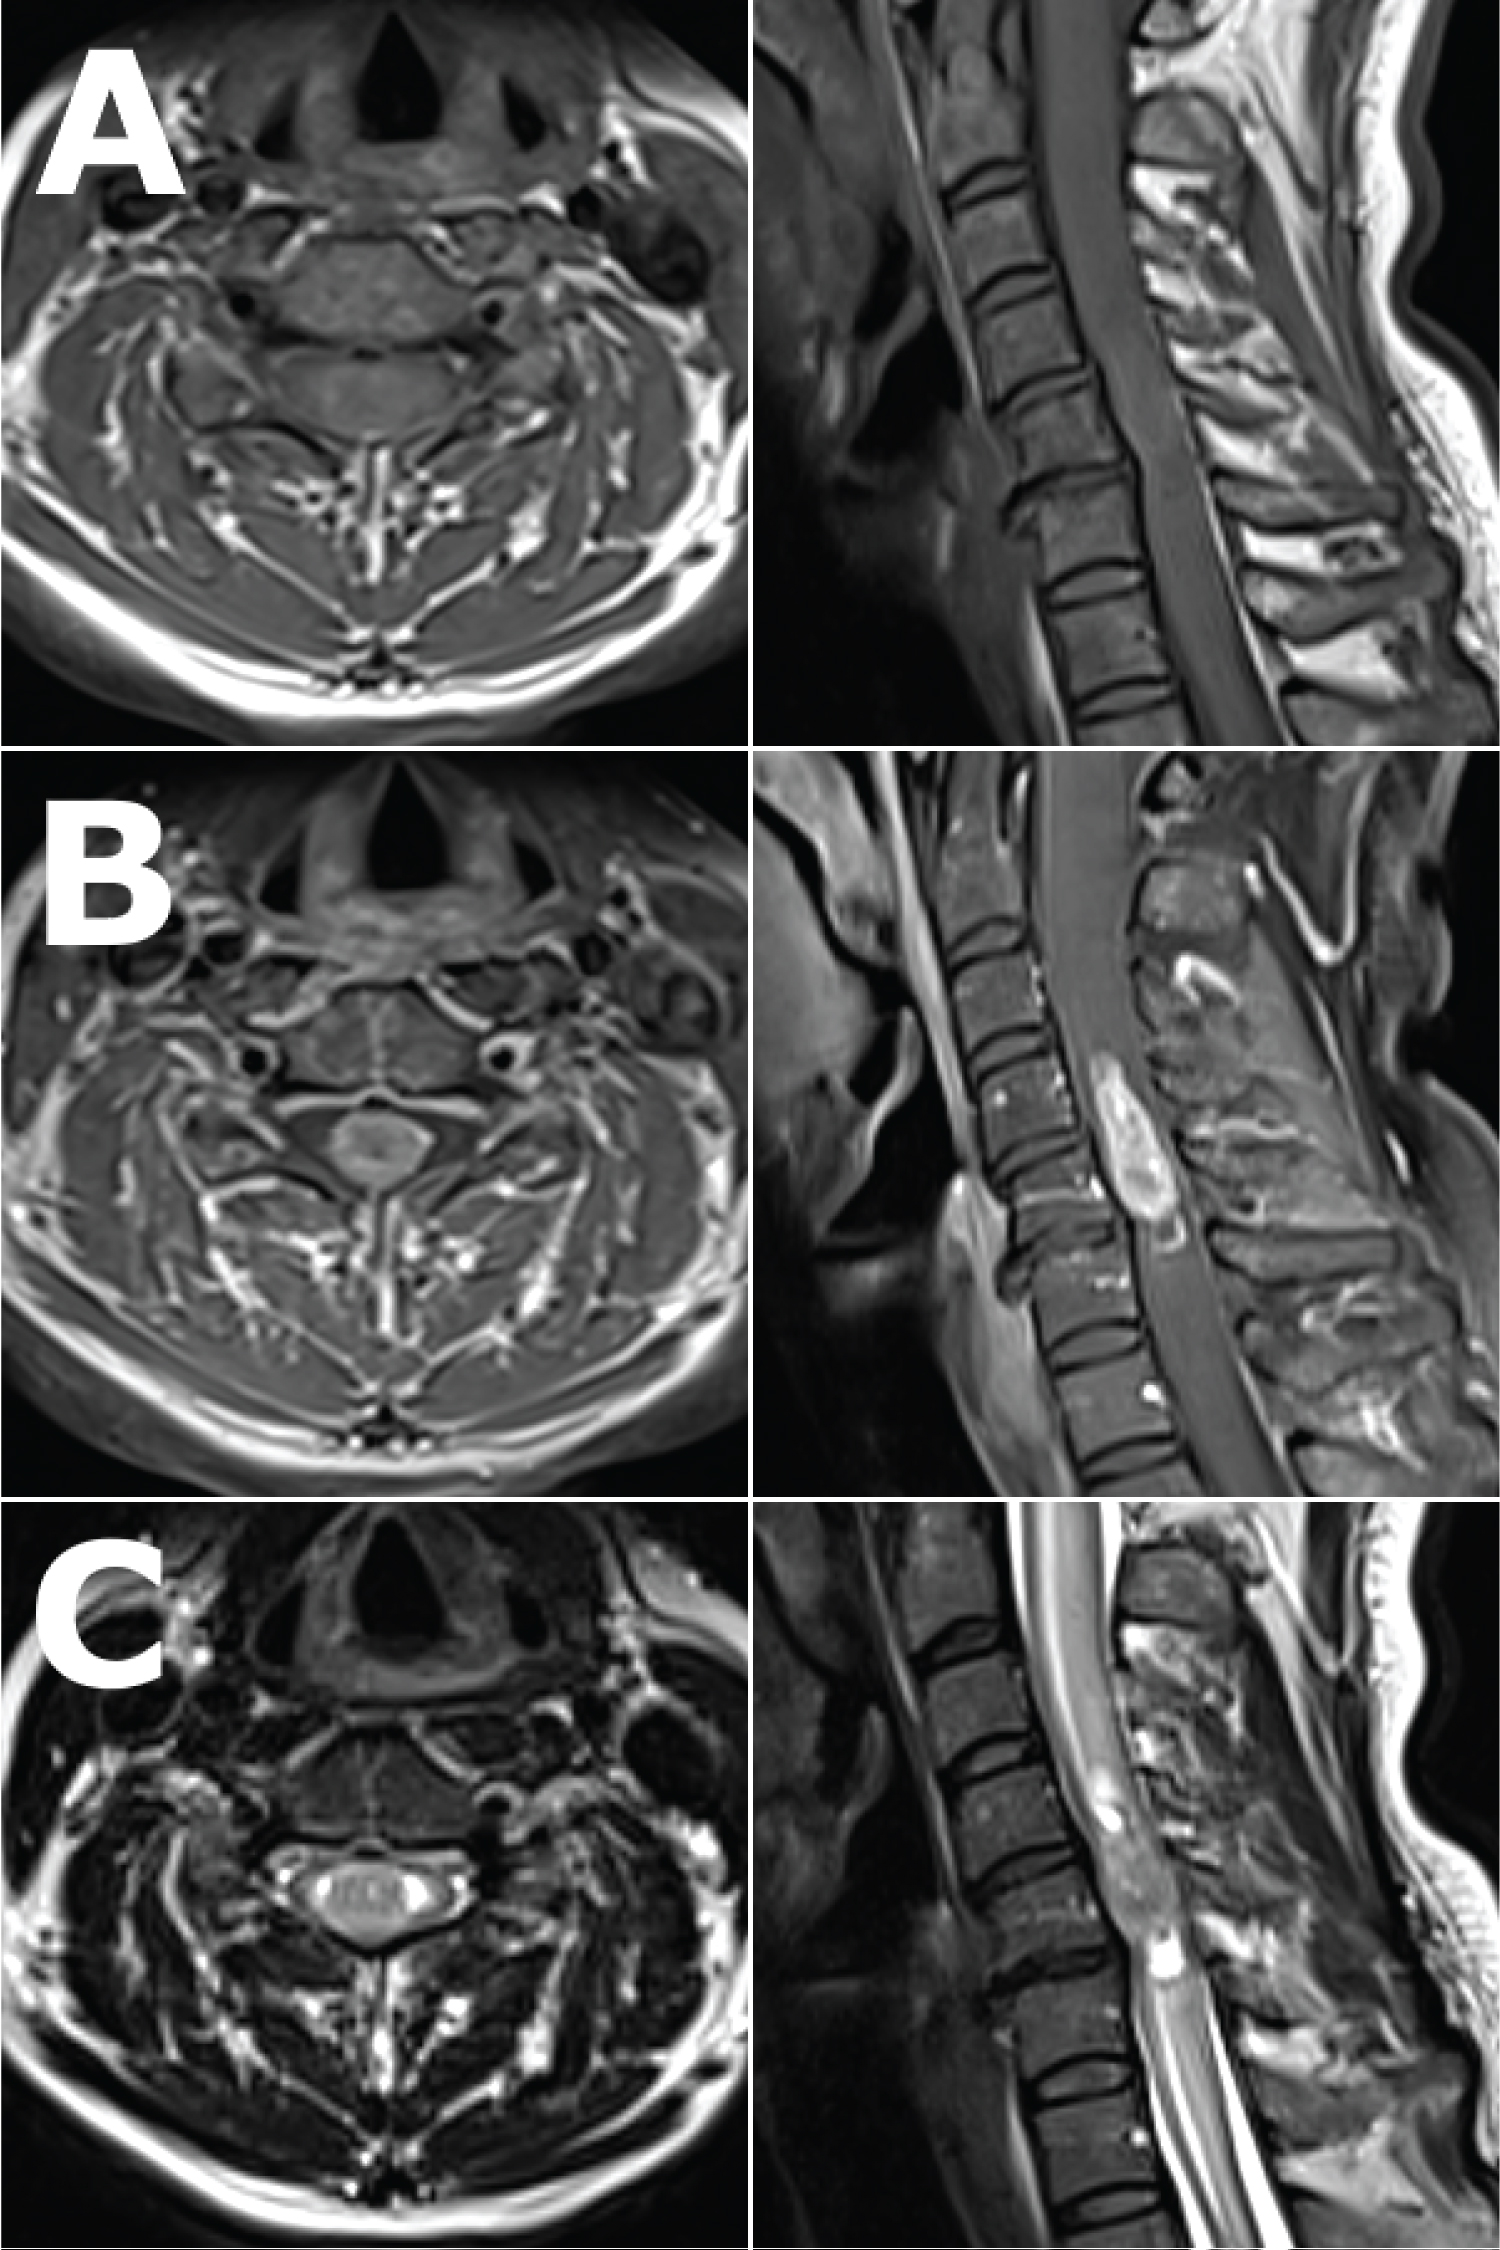

MRI imaging of her cervical spine (Figure 1) revealed an intramedullary lesion from C4 to C6, which was relatively well demarcated post-Gadolinium enhancement, with the radiological differential diagnosis including an ependymoma or astrocytoma. There was also significant associated oedema within the cervical spinal cord. Given the imaging findings and clinical progression, surgery was performed.

Figure 1: Pre-operative axial (left) and sagittal (right) views of the cervical spine MRI showing the lesion. T1 weighted images, A) pre and B) post- Gadolinium enhancement, showing a well-defined, T1 isointense but homogenously enhancing intramedullary lesion from C4 to C6, occupying most of the spinal canal at the level of C5. C) T2 weighted images showing the same lesion, which is T2 isointense with tiny spotty T2 hyperintensities within, splaying the normal spinal cord circumferentially around it at the level of C5, with associated syringomyelia most evident at the superior and inferior ends of the lesion, and with marked associated spinal cord oedema as evidenced by T2 signal change from C1 to T1. View Figure 1

Astroblastoma was once thought to be confined to the brain with some reports of metastases to the spine [8,9]. Primary astroblastoma of the brainstem and spinal cord has only recently been described [3,4,10-12]. Patients present with myelopathy or focal neurological deficit corresponding to the spinal level of disease [4]. The imaging appearances are fairly consistent - T1 weighted MRI shows a homogenously enhancing well circumscribed lesion, and T2 weighted MRI may show small cysts within a T2 iso to slightly hyperintense lesion with associated spinal cord oedema [3,4,10-12]. Progression of disease ranges from slow over months such as in the current case to very quickly over days to weeks [11]. Watchful waiting has been trialled but ultimately all cases required surgery and adjuvant treatment due to clinical and radiological progression of disease [10].